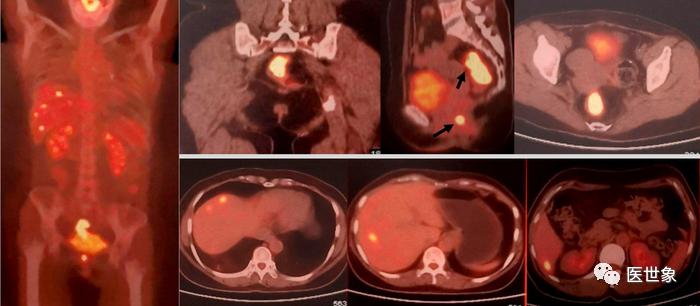

肝脏是结直肠癌血行转移最主要的靶器官,结直肠癌肝转是结直肠癌治疗的难点之一。

约有 15%~25% 结直肠癌患者在确诊时即合并有肝转移,另15%~25%的患者将在结直肠癌原发灶根治术后发生肝转移,其中绝大多数(80%~90%)的肝转移灶初始无法获得根治性切除。

肝转移是结直肠癌患者最主要的死亡原因,未经治疗的肝转移患者的中位生存期仅6.9个月,无法切除患者的5年生存率低于5%,而肝转移灶能完全切除[或可以达到“无疾病证据(NED)”状态]患者的中位生存期为35个月,5 年生存率可达 30%~57%。